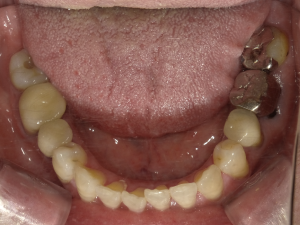

70代 女性 インプラント治療(GBR)

| 年代・性別 | 70代・女性 |

|---|---|

| 主訴 | 抜歯適応になってしまった所にインプラント治療希望。 |

| 部位 | 右上3・5(右上345のブリッジ)、右下6・7 左上4・6(左上456のブリッジ)、左下6・7 |

| 治療期間 | 約14ヶ月 |

| 費用 | ¥3,740,000(税込) |

| 副作用・リスク |

|